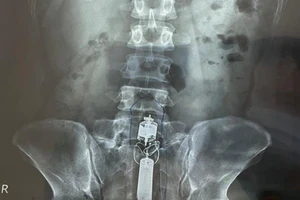

Nam thanh niên 20 tuổi bị tai nạn giao thông, gãy dương vật

18/01/2021 22:27